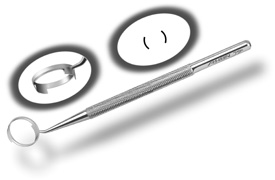

corneal mire. A simple handheld device such as the Maloney (Storz, Katena) or

Nichamin (Mastel Precision) keratoscope

works well, or a more robust and well-defined mire may be obtained through

an elaborate microscope-mounted instrument such as the Mastel Ring

of Light (Mastel Precision). Another common way in which the

steep meridian is marked utilizes a Mendez Ring or similar degree gauge

that is aligned with the previously placed limbal orientation mark, and

the cylinder axis is then located on the 360-degree gauge. The LRI should be placed at the most peripheral extent of clear corneal